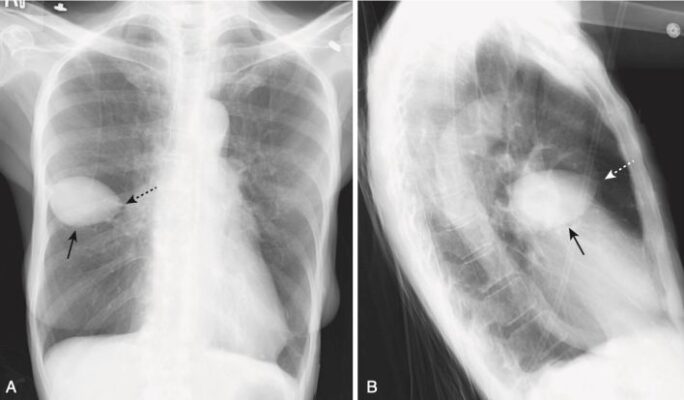

U giả phổi ở rãnh liên thuỳ (Fissural Pseudotumors)

- Các khối u giả là những tụ dịch màng phổi có bờ sắc rõ nằm hoặc giữa các lớp một rãnh liên thuỳ phổi hoặc ở vị trí dưới màng màng phổi ngay dưới rãnh. Đó là dịch thấm hầu như luôn xảy ra ở bệnh nhân suy tim sung huyết.

- Các dấu hiệu hình ảnh của một khối u giả là đặc trưng, vì vậy không nên nhầm chúng với một khối u thực sự.

- Chúng có hình thấu kính, thường xuất hiện nhất ở rãnh liên thuỳ bé (75%) và thường có đầu nhọn ở mỗi bên, nơi chúng lách vào rãnh liên thuỳ, giống như hình dạng của quả chanh. Chúng không có xu hướng di chuyển tự do khi thay đổi tư thế bệnh nhân.

- Chúng biến mất khi bệnh lý nền (thường là suy tim sung huyết) được điều trị, nhưng có xu hướng tái phát ở cùng một vị trí mỗi khi suy tim tái phát (Hình 14).